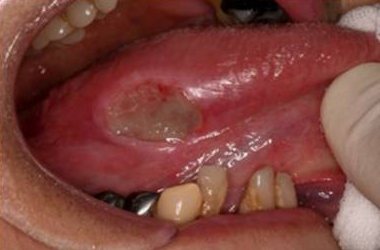

いわゆる口内炎

出典

img

1: 著者提供